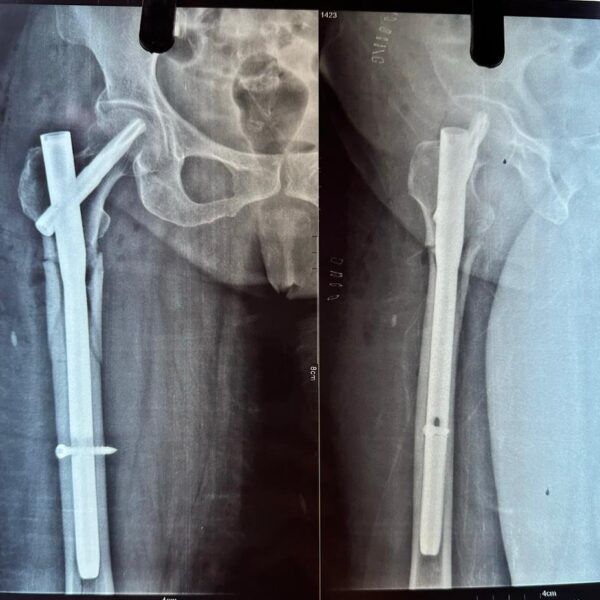

Moments That Mark Meaningful Recovery

Witness real patient transformations at The Ortho Clinic through images that reflect successful treatments and restored mobility.